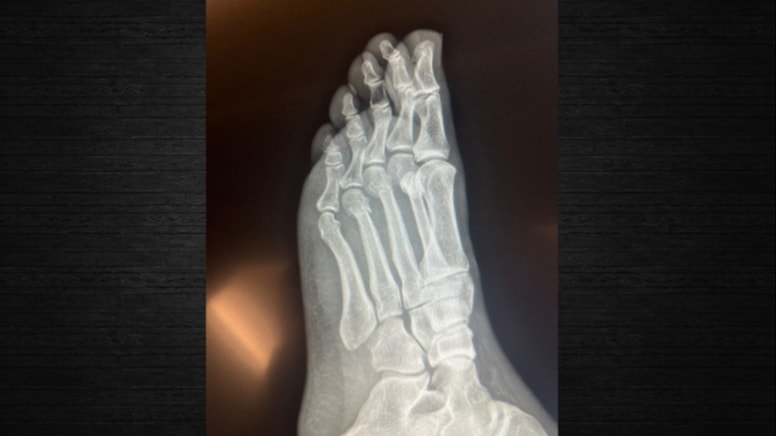

Ayağı kırılan CHP lideri Özel'in alkollüyken düştüğü ya da vurulduğu iddia edildi. Özel de bu iddiaların ardından ayağının kırık olduğunu gösteren röntgeni paylaştı.

Özgür Özel. CHP lideri Özgür Özel’in ayağı kırıldı ama bu olay polemiğe neden oldu. Çünkü birçok hesap aslında ayağından vurulduğunu ya da alkollüyken düştüğünü söyledi. Birçok iddianın ardından röntgeni paylaşabileceğini söyleyen Özel söylentiler durulmayınca ayağının kırık olduğunu gösteren röntgeni açıkladı.

Özgür Özel’in paylaştığı röntgen.